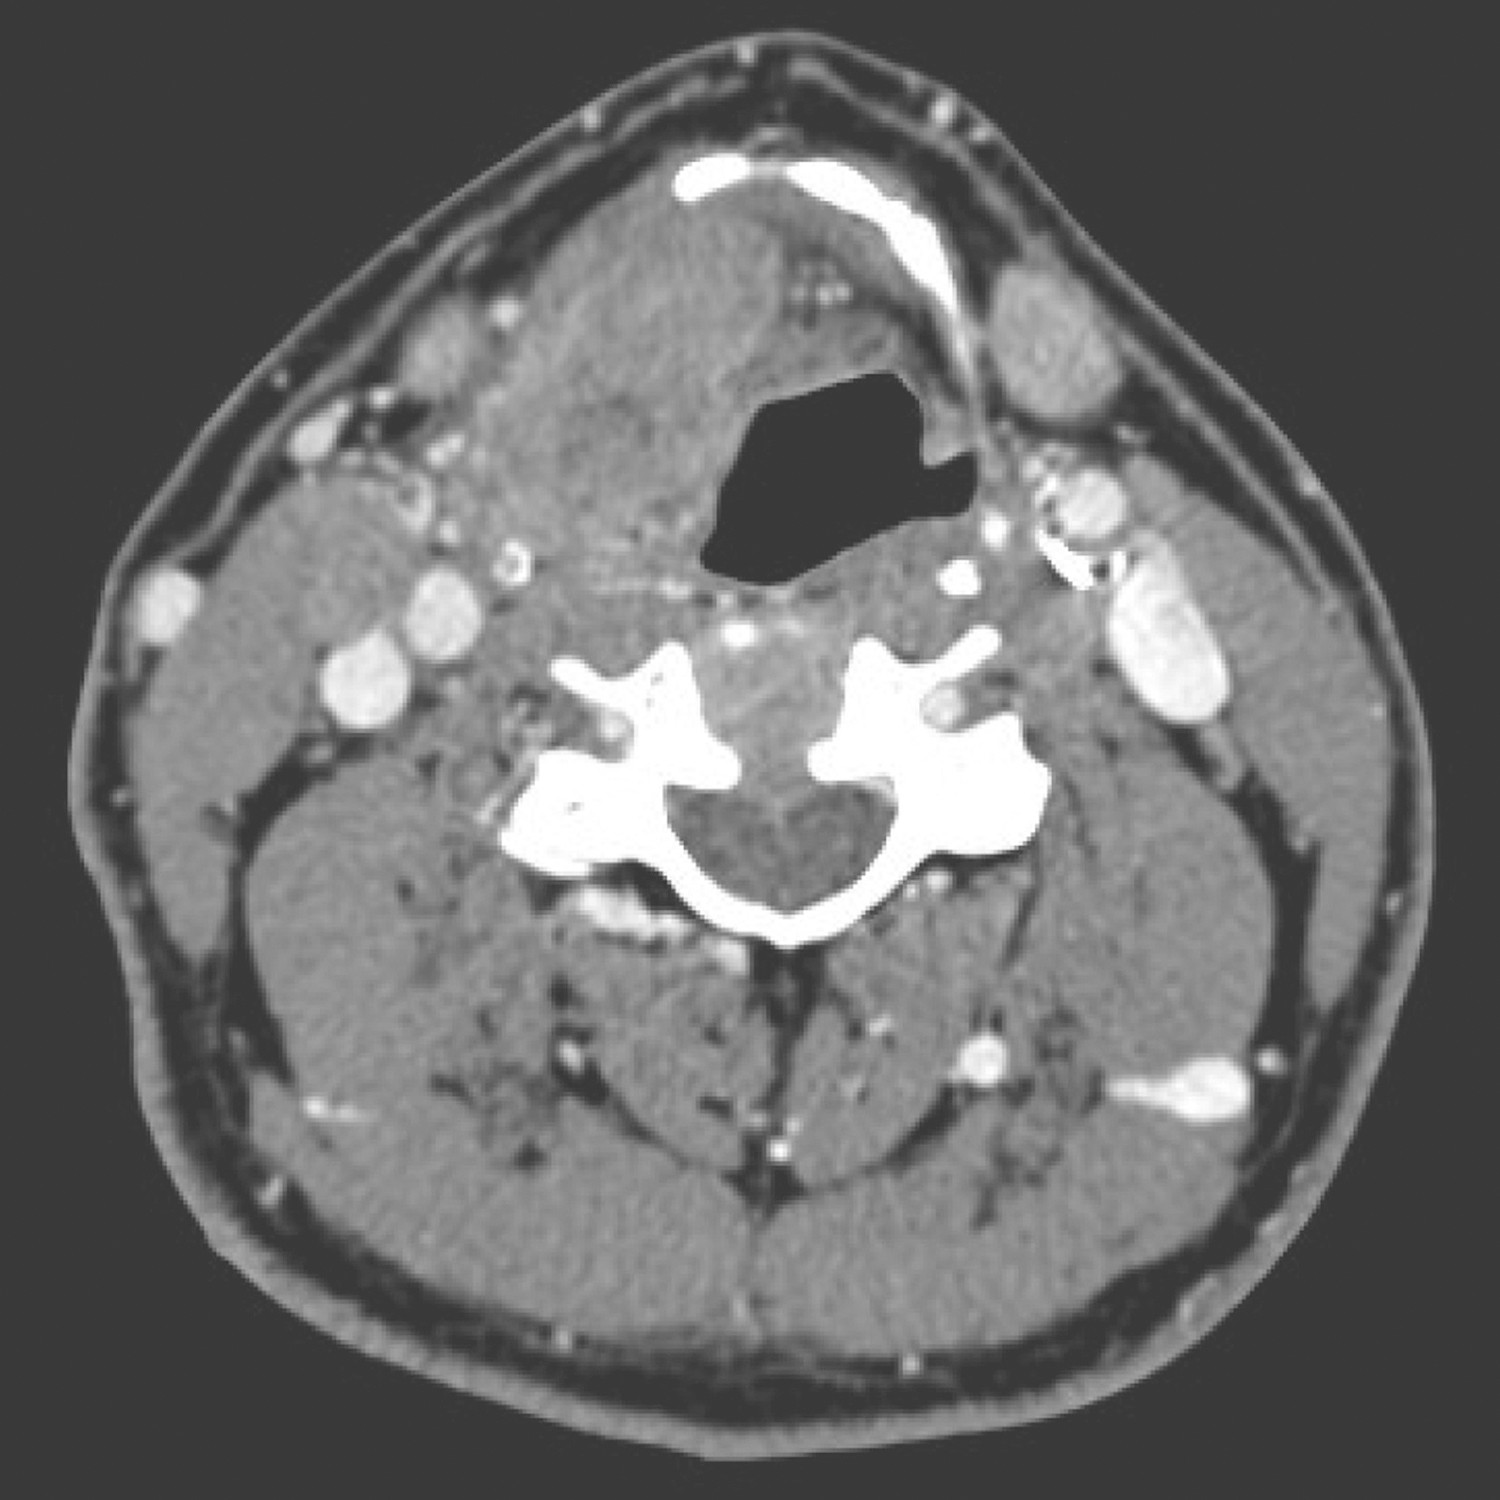

2.2014年1月10日颈胸部强化CT

右侧梨状窝内侧壁、右侧杓会厌皱襞局部软组织增厚,约4cm×3cm,形态不规则,累及右侧声门旁间隙和会厌前间隙,可见强化。右侧Ⅱ区胸锁乳突肌内侧可见数枚肿大淋巴结,约2cm×1.5cm大小,可见环形强化,边界不清(图4~图6),纵隔、双肺门未见肿大淋巴结。CT诊断:下咽恶性肿瘤并颈部淋巴结转移表现。

图4右侧Ⅱ区胸锁乳突肌内侧可见数枚肿大淋巴结

图5右侧梨状窝内侧壁、右侧杓会厌皱襞局部软组织增厚

图6累及右侧声门旁间隙